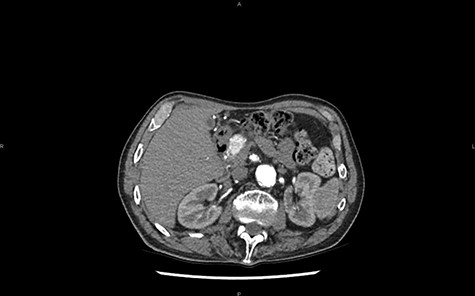

The final diagnostic assumption is an NET of the pancreas with a single metastatic hepatic lesion (segment II). During surgical exploration another hepatic lesion is found (segment V). As a result, a cephalic duodenopancreatectomy is performed with a resection of the two hepatic lesions.

MRI in coronal section, T2 phase: visualization of a compression of the main pancreatic duct.